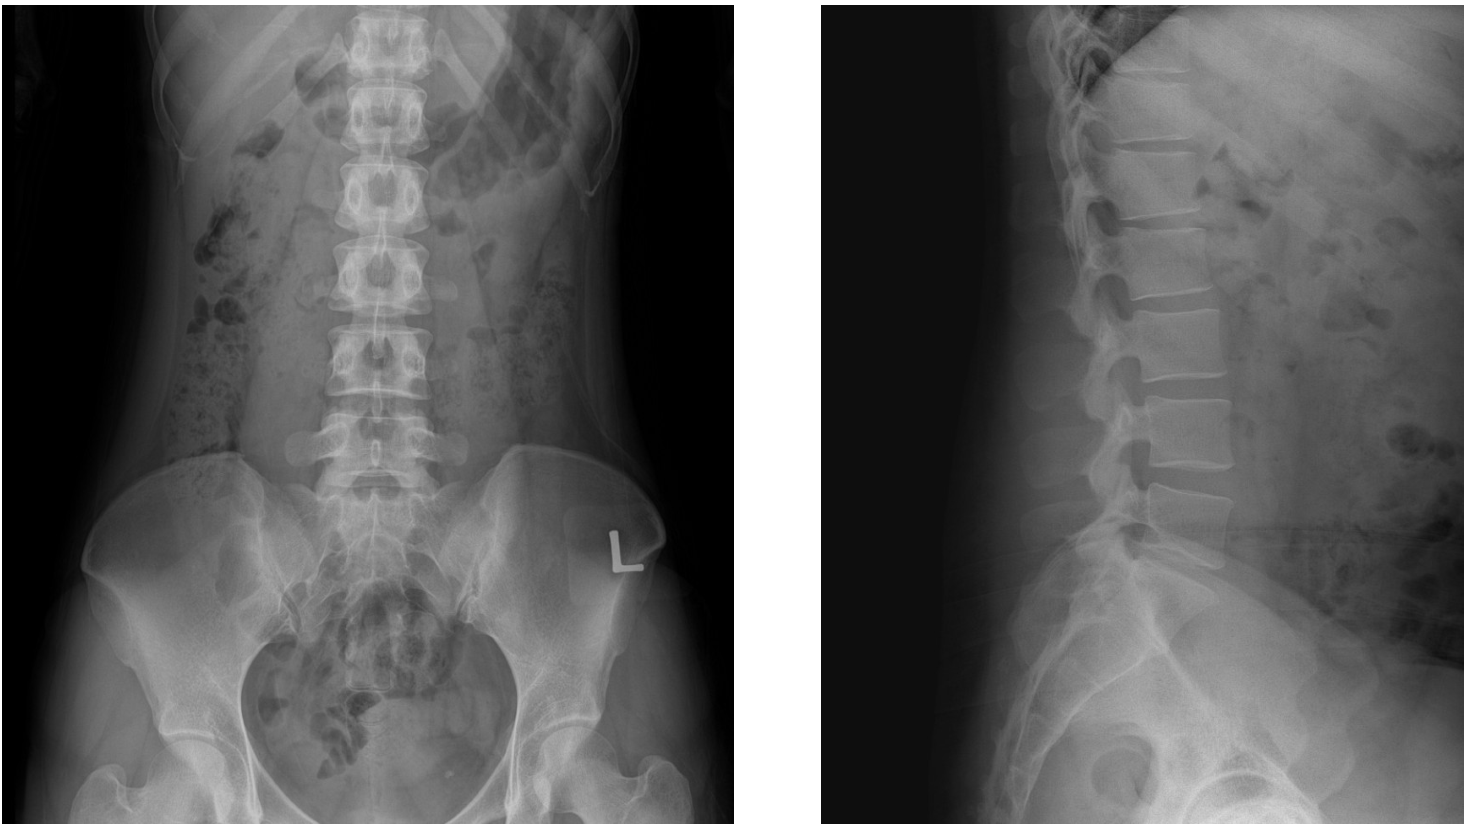

人體腹腔成像示意圖(正拍、側拍)